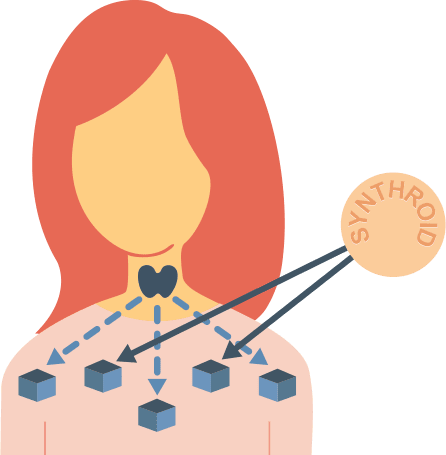

بیشتر بخوانید »عصبانیت زیاد نشانه تیروئید است؟

عصبانیت زیاد نشانه تیروئید است؟ دکتر رضا کریمی: عصبانیت، ناراحتی، تشویش و احساس عدم تمرکز کافی روحی علائمی است که میتواند نشانه بیماری تیروئید باشد.هورمونهای تیروئید تولید انرژی و حرارت در بدن را افزایش میدهد و به همین دلیل اگر این هورمونها کم یا زیاد باشند، در هر دو حالت، بیمار انرژی و تمرکز ندارد. در واقع بیمار دچار پرکاری …

باورهای اشتباه درباره “تیروئید” یک فوق تخصص غدد و متابولیسم گفت: بعضی از سالمندان مبتلا به پرکاری تیروئید، نه تنها کاهش وزن پیدا نمیکنند، بلکه وزنشان بیشتر هم میشود.دکتر حسن گنجیزاده زواره اظهار کرد: گاهی اوقات باورهای رایجی درباره تیروئید وجود دارد که کاملا اشتباه است.وی با بیان اینکه بیشتر بیمارانی که تیروئیدشان مشکل دارد، گواتر (بزرگی غیر طبیعی تیروئید) …